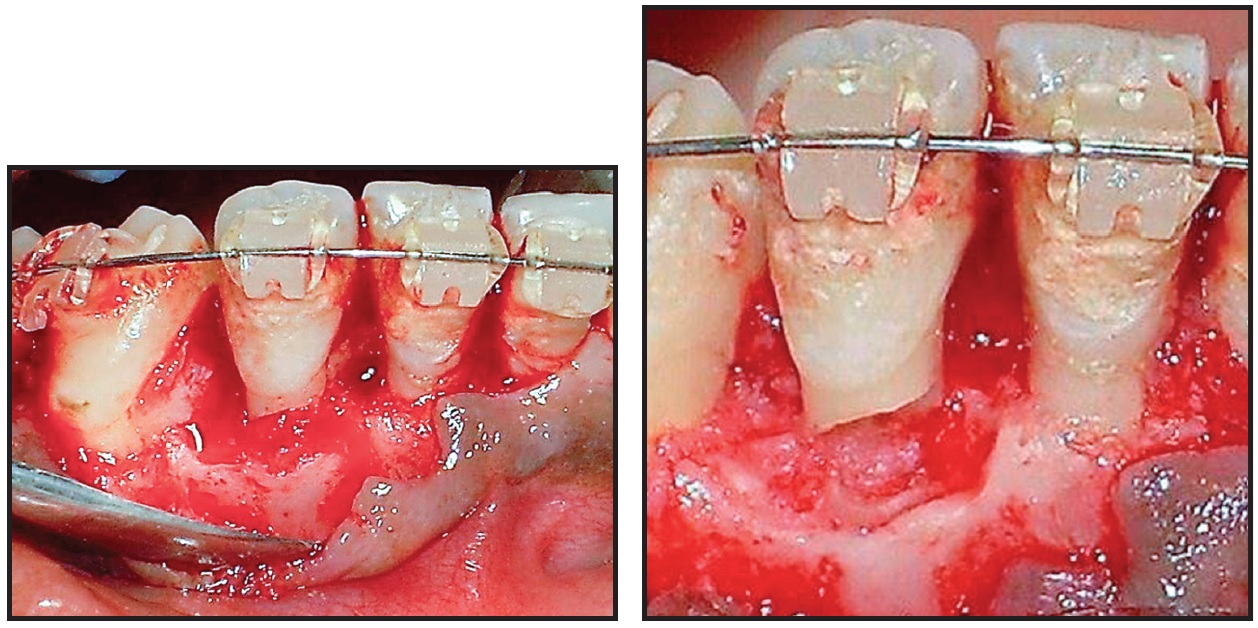

A 40-year-old male was referred by his dentist because of esthetic and functional problems. Intraoral examination showed lower anterior crowding accompanied by tartar deposits and a crossbite of the upper right lateral incisor with the lower right lateral incisor and canine (Fig. 1).

Fig. 1 40-year-old male patient with lower anterior crowding and crossbite, deviation of mandibular midline, and inflammatory gingival recession of lower right lateral incisor before treatment.

The lower right lateral incisor exhibited Class II mobility and inflammatory gingival recession on the labial side. The patient had a Class I occlusal relationship with a 4mm overjet and a 2.5mm overbite; the mandibular midline was deviated to the right.

Functional examination revealed an abnormality in the path of closure, resulting in deviation of the mandible to the right. A masticatory dysfunction was indicated by the occlusal trauma to the lower right lateral incisor, but the panoramic radiograph showed no evidence of root lesions.